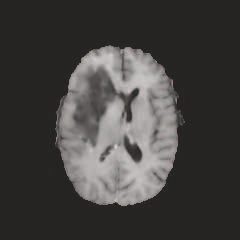

Multi-modal medical image completion has been extensively applied to alleviate the missing modality issue in a wealth of multi-modal diagnostic tasks. However, for most existing synthesis methods, their inferences of missing modalities can collapse into a deterministic mapping from the available ones, ignoring the uncertainties inherent in the cross-modal relationships. Here, we propose the Unified Multi-Modal Conditional Score-based Generative Model (UMM-CSGM) to take advantage of Score-based Generative Model (SGM) in modeling and stochastically sampling a target probability distribution, and further extend SGM to cross-modal conditional synthesis for various missing-modality configurations in a unified framework. Specifically, UMM-CSGM employs a novel multi-in multi-out Conditional Score Network (mm-CSN) to learn a comprehensive set of cross-modal conditional distributions via conditional diffusion and reverse generation in the complete modality space. In this way, the generation process can be accurately conditioned by all available information, and can fit all possible configurations of missing modalities in a single network. Experiments on BraTS19 dataset show that the UMM-CSGM can more reliably synthesize the heterogeneous enhancement and irregular area in tumor-induced lesions for any missing modalities.